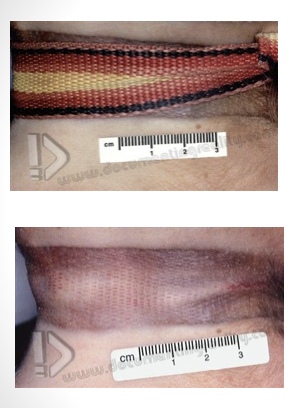

ligature strangulation

pressure on neck applied by object tightened by force other than body weight

most commonly associated with rape

death due to occlusion of carotid arteries with cerebral hypoxia

blood gets to head but can’t drain = congested face, numerous petechiae of sclera and conjunctiva, periorbital and face skin too

manual strangulation

strangulation from hand, forearm or another limb; occludes vessels on neck

congestion of face, petechial hemorrhages, fingernail marks, hemorrhage in the strap muscles, hyoid fracture, abrasions/contusions on neck

can’t say antemortem if no significant hemorrhage around hyoid/thyroid